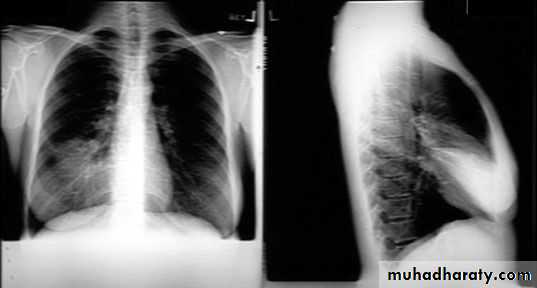

NORMAL PA view

Lateral view position